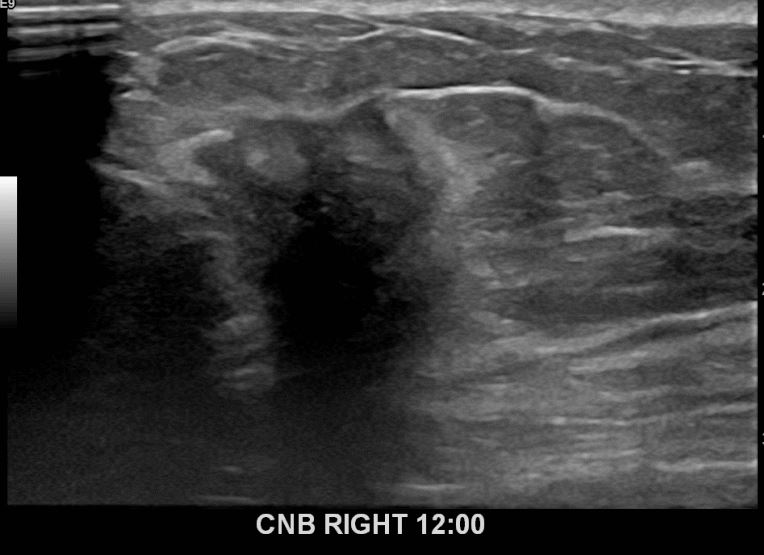

아산유외과 개원후 640번째 유방암진단

상기환자 외부검사상 이상소견으로 내원하신 50대여성으로 우측 유방의 의심스러혹

조직검사시행해 유방암 진단되었읍니다